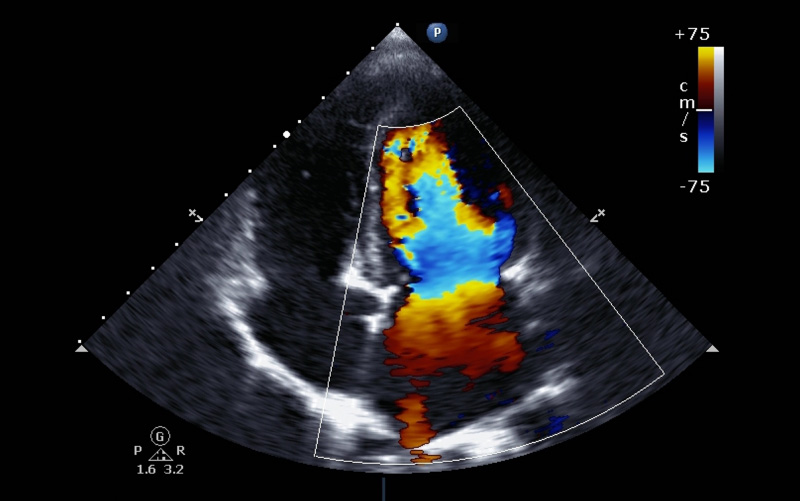

Tapping into the technology behind facial recognition programs and self-driving cars, researchers in a new study have taught computers key elements of assessing echocardiograms, potentially simplifying an otherwise extensive process now done by humans.

Researchers created algorithms to recognize images and potential heart problems that echocardiograms commonly capture, including enlarged chambers, diminished pumping function and even some uncommon diseases.

Echocardiograms help doctors evaluate heart function by using sound waves to create snapshots of every part of the organ. Because they don’t give off radiation and can be given easily in a medical office, they’re a popular imaging choice to diagnose heart disease. But, Dr. Rahul Deo, the study’s senior author, said they’re not done enough because the process of assessing results is long and taxing.

Looking at 14,035 echocardiograms, collected over 10 years from a University of California San Francisco database, researchers fed 23 views of each heart chamber from every test into a computer algorithm. They also provided labels for every specific, identifiable image captured.